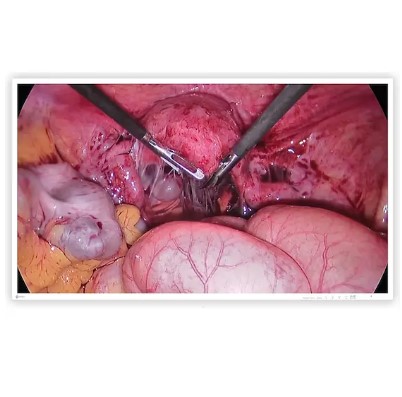

CuratOR EX4342-3D to 43-calowy monitor przeznaczony do montażu na wózkach medycznych. Oferuje rozdzielczość 4K UHD (3840 x 2160) i wyświetla obrazy chirurgiczne z doskonałą ostrością. Monitor wyposażono w funkcję automatycznego wykrywania sygnału wejściowego oraz tryby pracy PinP i PbyP.

EX4342-3D wiernie odtwarza obrazy stereoskopowe w rozdzielczości 4K UHD (3840 x 2160) przy wysokiej jasności do 700 cd/m², zapewniając zarówno szczegółowość, jak i głębię w endoskopii i mikrochirurgii.

Szeroki gamut kolorów

Podczas zabiegu chirurg musi być w stanie dostrzec subtelne różnice między kolorami. Model EX4342-3D obsługuje przestrzeń barw BT.2020, dlatego wyświetlając na nim obrazy uchwycone kamerami zgodnymi z tym standardem, można bez trudu rozróżnić odcienie czerwieni i żółci.

Kompatybilność z HDR

HDR (ang. High Dynamic Range) to technologia umożliwiająca wyświetlanie kolorów w sposób zbliżony do percepcji ludzkiego oka, niedostępna dla standardowych materiałów wideo. Do obsługi szerszej rozpiętości tonalnej monitor EX4342-3D wykorzystuje krzywe PQ (Perceptual Quantization) i HLG (Hybrid Log Gamma). Obrazy pochodzące z kamer endoskopowych kompatybilnych z technologią HDR będą więc wyświetlane prawidłowo, bez utraty cieni na ciemnych obszarach.